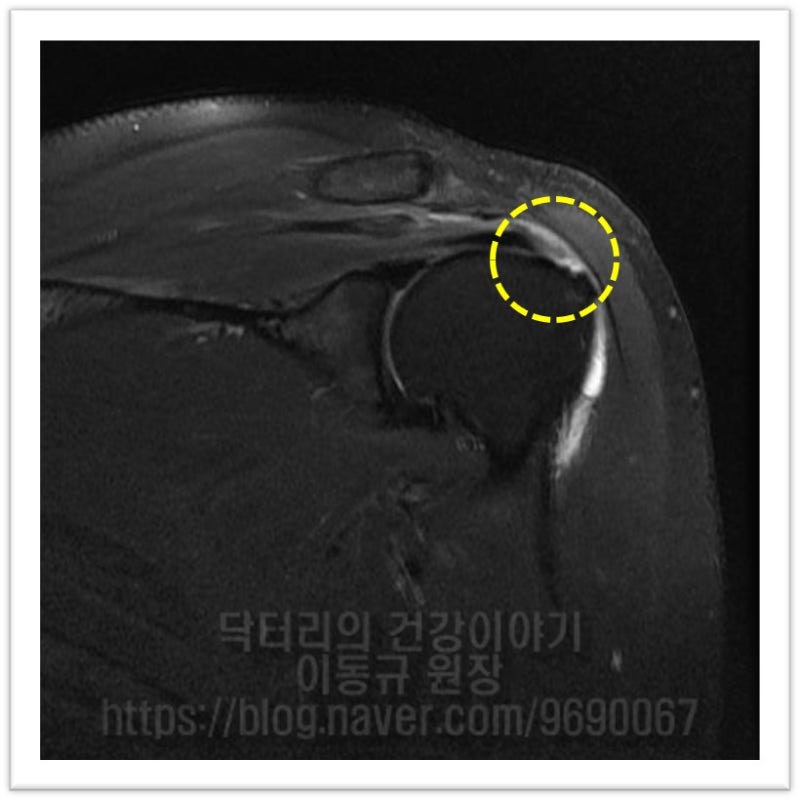

MRI 상 파열 사이즈도 크지 않고 힘줄 상태로 그렇게 나쁘게 보이지 않습니다. 관절경을 통하여 봉합술을 하기로 하였습니다.

이 환자의 경우 나이가 비교적 젊음에도 불구하고 힘줄의 상태가 매우 좋지 않았습니다. 아마 수년간 통증주사(아마도 스테로이드)만 맞고 팔을 계속 사용하면서 회전근개 손상은 점점 진행되고 퇴행성 변화가 가속화 된 것으로 사료됩니다. 수술 후 6주에 MRI 검사를 시행하였습니다.